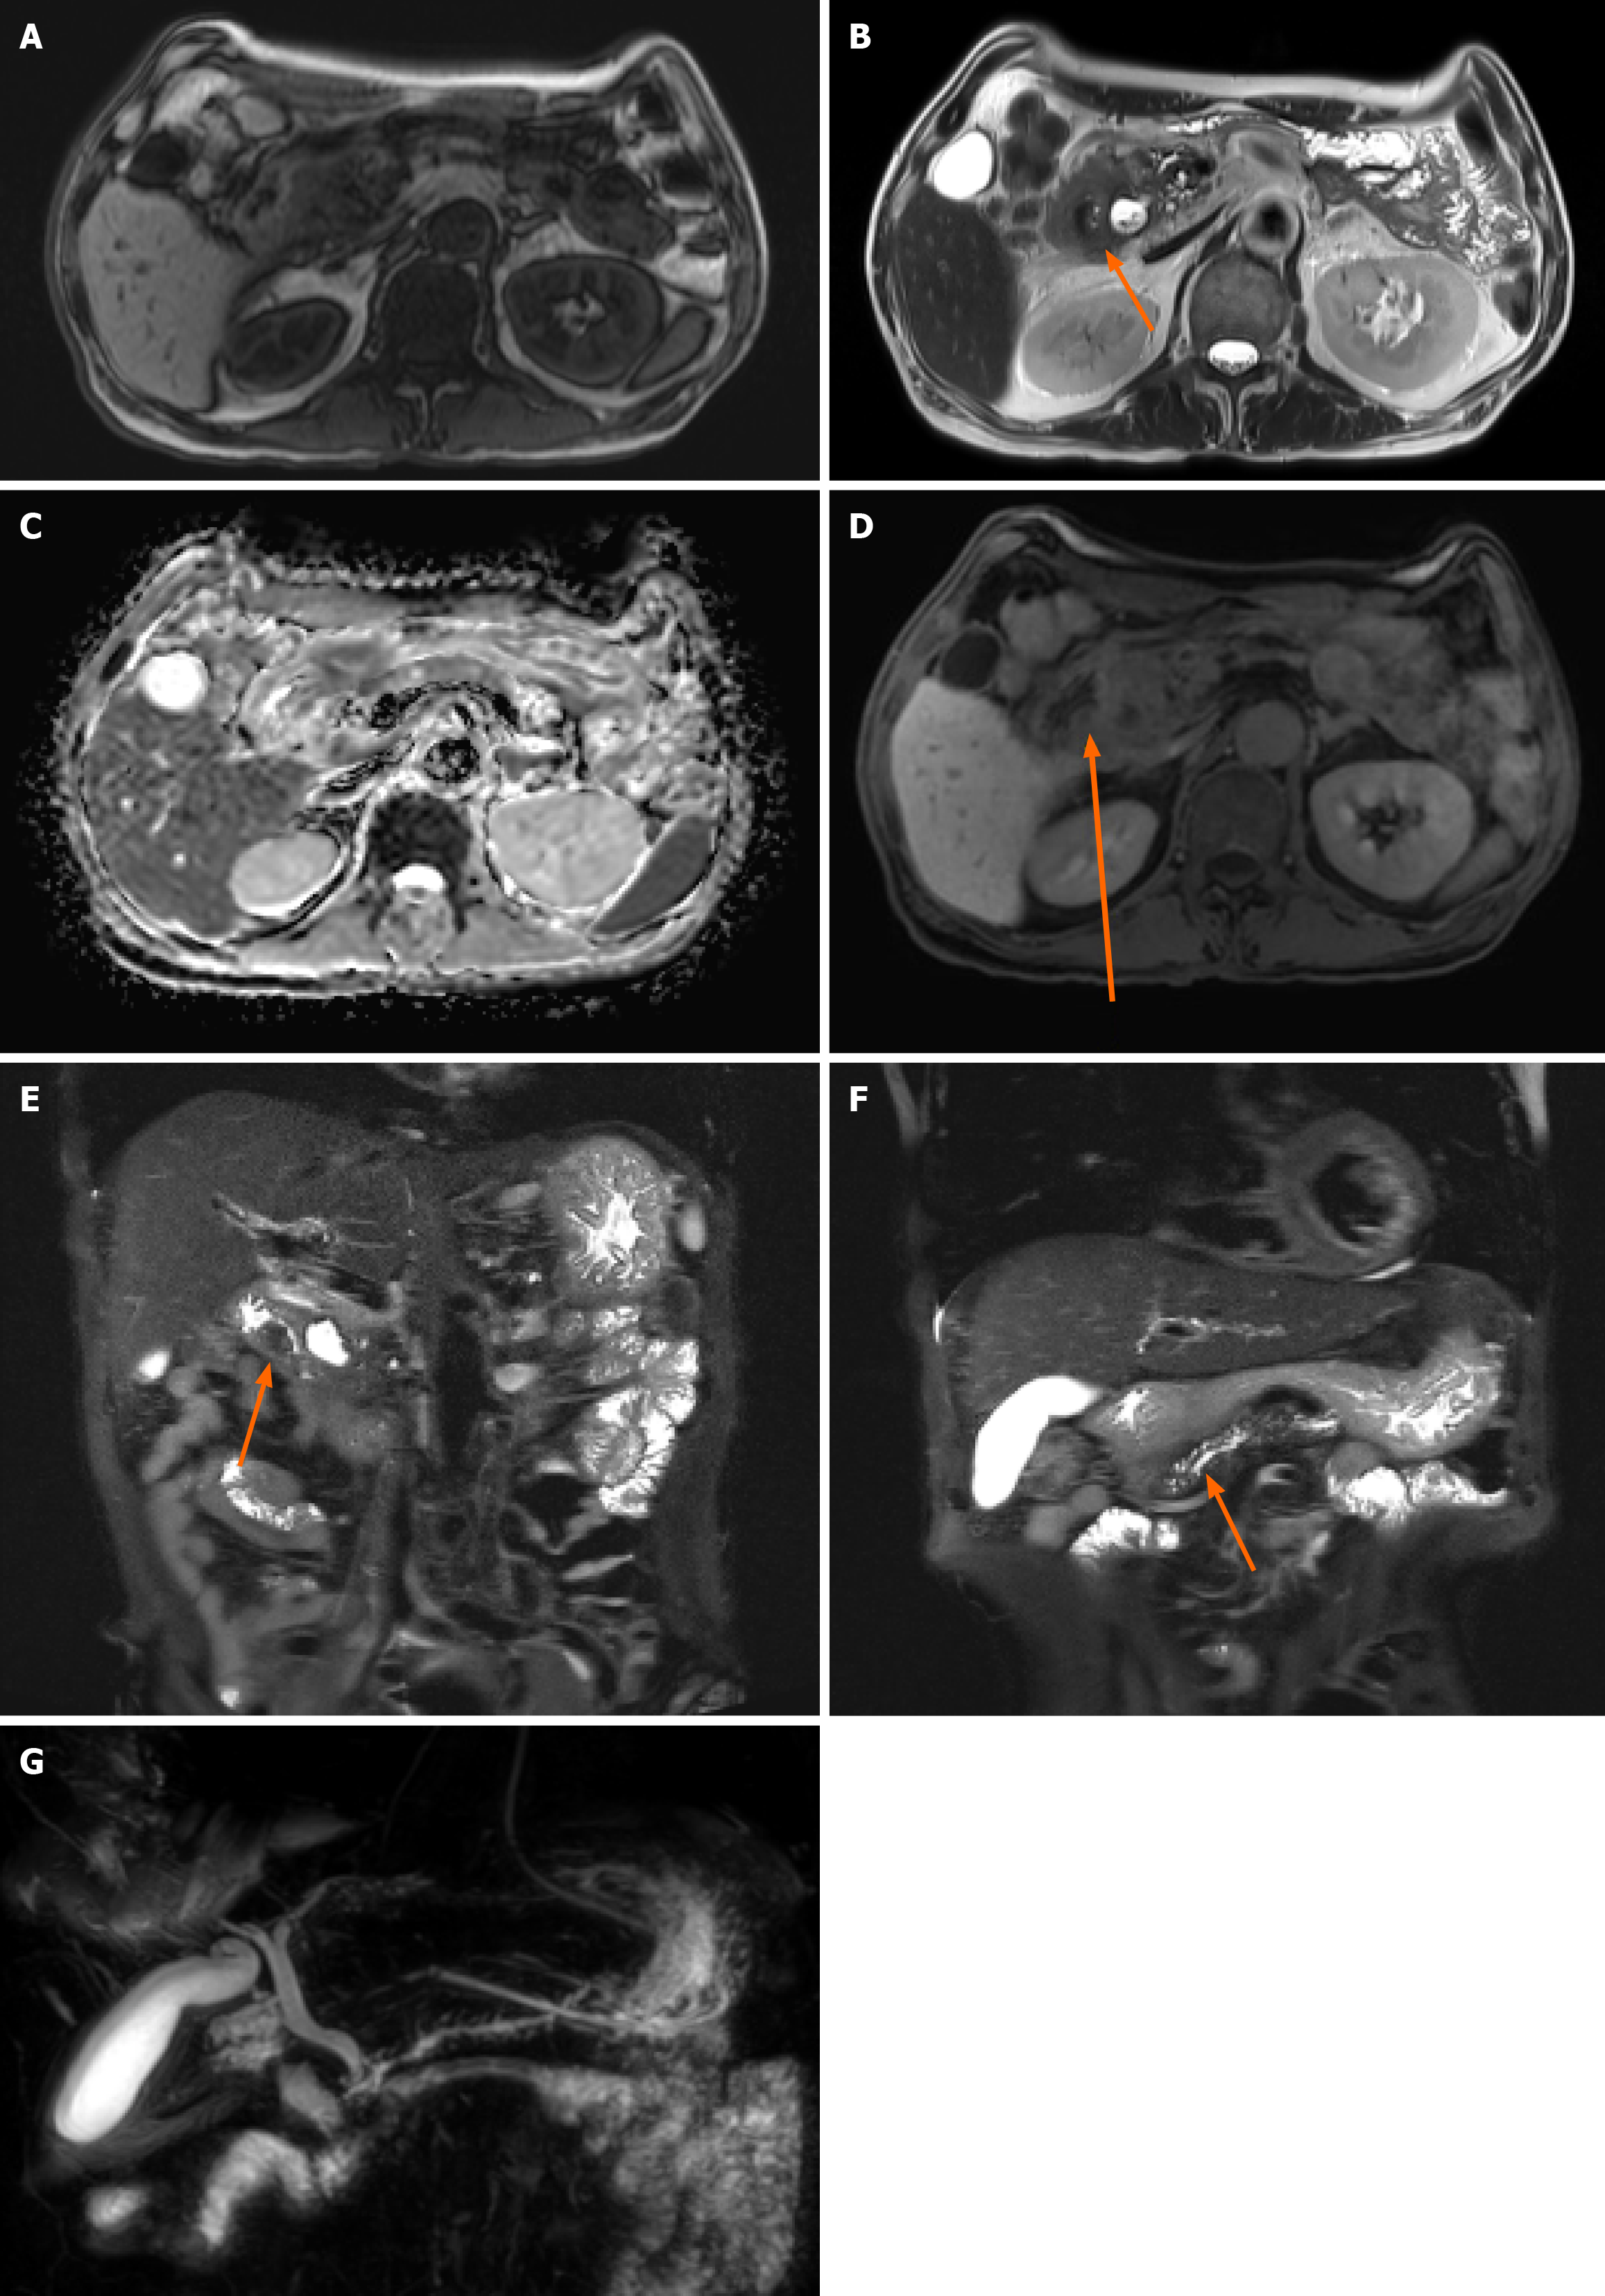

Figure 2 Pancreatic magnetic resonance imaging findings.

A: T1 weighted image; B: T2 weighted axial image; C: Diffusion weighted image; D: Vibe image; E and F: T2 weight coronal image; G: Magnetic resonance cholangiopancreatography. Magnetic resonance imaging showing a lesion in the ampulla of Vater with no clear T1 weighted and diffusion restriction image (A and C) but prominent enhancement, which is suspicious for ampulla of Vater cancer (B, D and E); magnetic resonance imaging showing main pancreatic duct upstream dilatation (F and G).